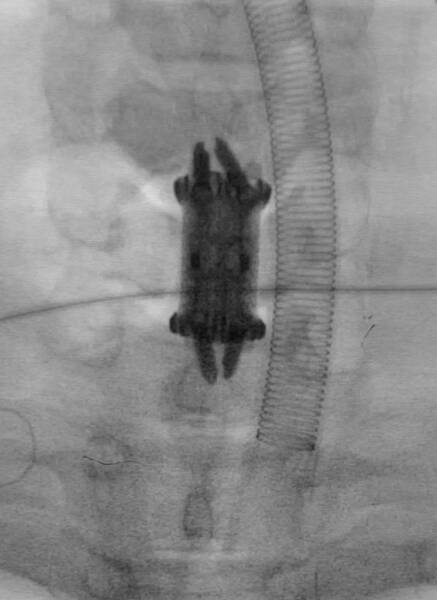

△術后

△手術中植入的自穩(wěn)型3D打印人工椎體